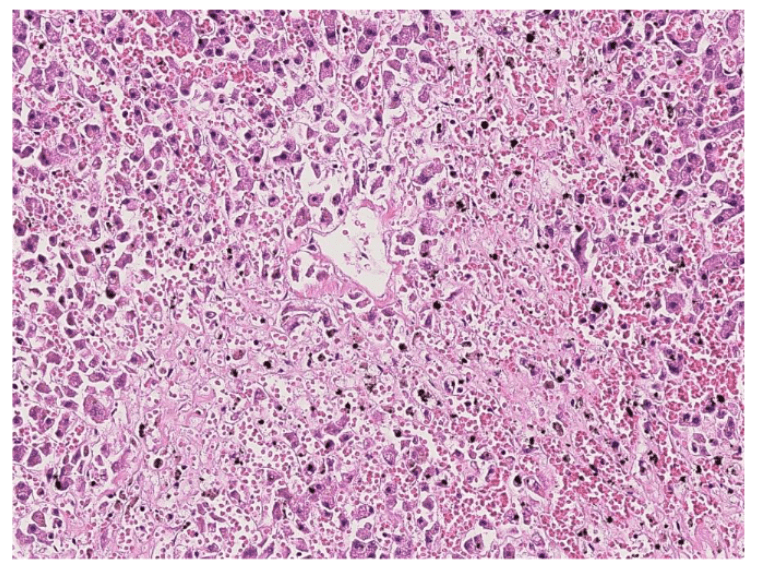

lung adenocarcinoma